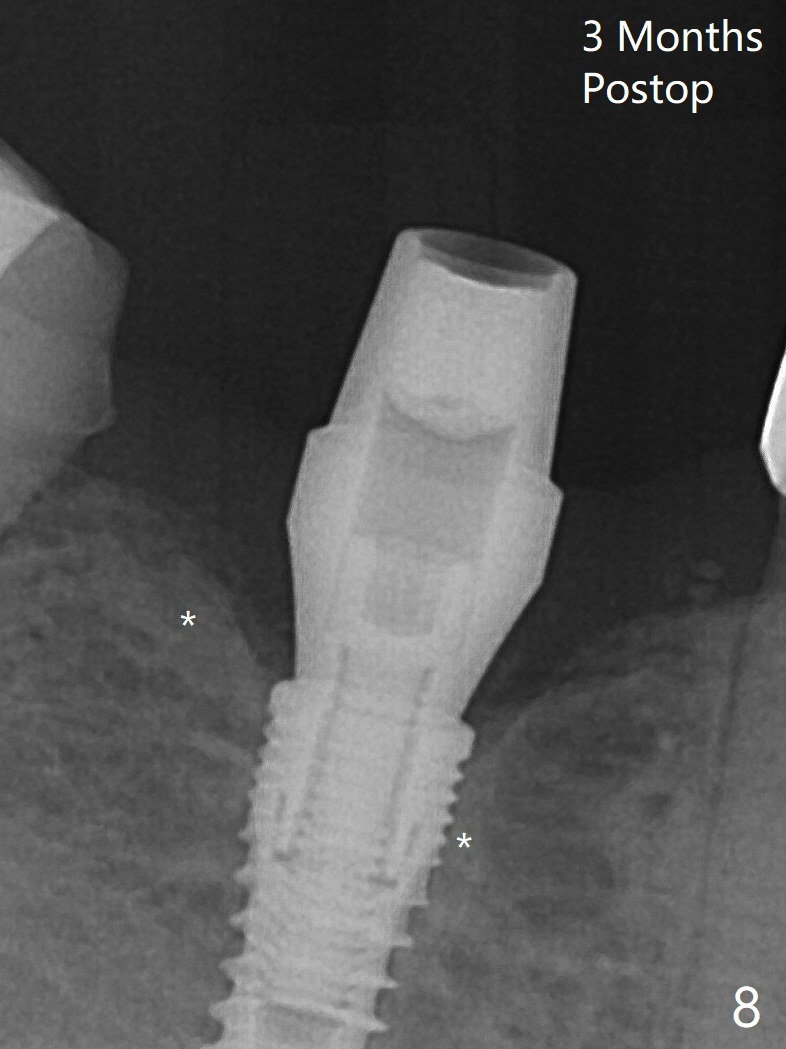

When a 3.8x12 mm SM implant is placed with 40 Ncm, there is 1-2 mm cortical bone buccolingually (primary stability, Fig.4,5). The thick cortices do not seem to be easy to be bent, i.e., expanded. There appears dense bone formation 3 months postop (Fig.8 *). One year post cementation, the crown at #31 needs recementation (Fig.9); the bone density next to the coronal implant increases (*).